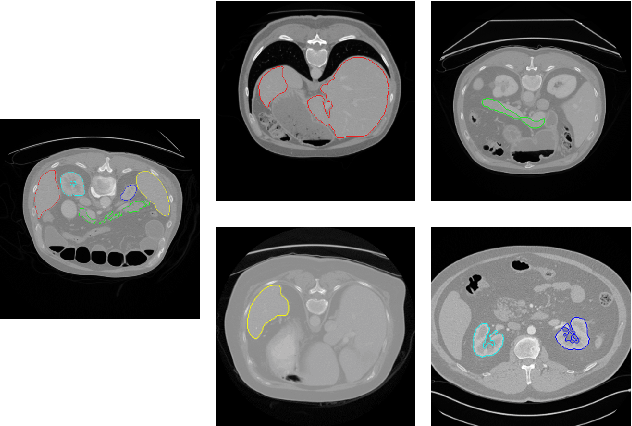

Abstract:Annotating multiple organs in medical images is both costly and time-consuming; therefore, existing multi-organ datasets with labels are often low in sample size and mostly partially labeled, that is, a dataset has a few organs labeled but not all organs. In this paper, we investigate how to learn a single multi-organ segmentation network from a union of such datasets. To this end, we propose two types of novel loss function, particularly designed for this scenario: (i) marginal loss and (ii) exclusion loss. Because the background label for a partially labeled image is, in fact, a `merged' label of all unlabelled organs and `true' background (in the sense of full labels), the probability of this `merged' background label is a marginal probability, summing the relevant probabilities before merging. This marginal probability can be plugged into any existing loss function (such as cross entropy loss, Dice loss, etc.) to form a marginal loss. Leveraging the fact that the organs are non-overlapping, we propose the exclusion loss to gauge the dissimilarity between labeled organs and the estimated segmentation of unlabelled organs. Experiments on a union of five benchmark datasets in multi-organ segmentation of liver, spleen, left and right kidneys, and pancreas demonstrate that using our newly proposed loss functions brings a conspicuous performance improvement for state-of-the-art methods without introducing any extra computation.